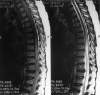

Results: TM presented either as the initial manifestation or within five years of the diagnosis of SLE. Most patients presented with a detectable sensory deficit at the thoracic level. In our 14 patients, 22% of the patients showed complete neurological recovery, whereas in the total patient population of 105 (our cases plus those reviewed in the literature), complete recovery was observed in 50%, partial recovery in 29% and no improvement or deterioration in 21%. Treatment with intravenous methylprednisolone followed by cyclophosphamide seemed to be most effective. Seventy per cent of the total patient population had abnormal magnetic resonance imaging findings. In our group of 14 patients, those with higher disease activity (measured by the SLAM) at onset of TM were treated more aggressively (for example, with plasmapheresis and intravenous pulse cyclophosphamide) V体育ios版. TM in our patients was associated with antiphospholipid antibodies in 43% of the cases as compared with 64% of the total patient population. Optic neuritis occurred in 48% of the total patient population with SLE and TM, suggesting an association. .